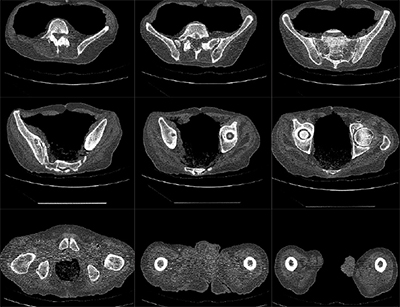

Total knee vs. partial knee replacement

Based on the severity of the arthritis in the knee, total or partial knee replacement may be recommended by a surgeon. Both procedures involve the orthopaedic surgeon guiding the Mako Robotic-Arm to remove diseased bone and cartilage.

- Mako Robotic-Arm Assisted Partial Knee replacement is a treatment option for adults living with early to mid-stage osteoarthritis (OA) that has not yet progressed to all three compartments of the knee. Depending on where the arthritis affects the knee, patients may have an implant inserted in any of the following areas:

- In comparison, Mako Robotic-Arm Assisted Total Knee replacement is a treatment option for adults living with mid to late-stage osteoarthritis of the knee. With Mako Total Knee replacement, the entire knee joint is replaced and the surgeon inserts a Triathlon Total Knee implant. With over a decade of clinical history, Triathlon knee replacements are different than traditional knee replacements because they are designed to work with the body to promote natural-like circular motion.5-8